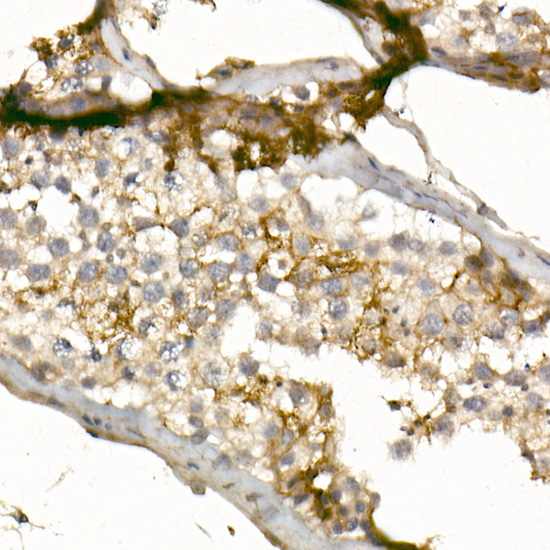

Application, WB, IHC, IF; Recommended dilution: WB 1:500 - 1:2000, IHC 1:50 - 1:200, IF 1:50 - 1:200